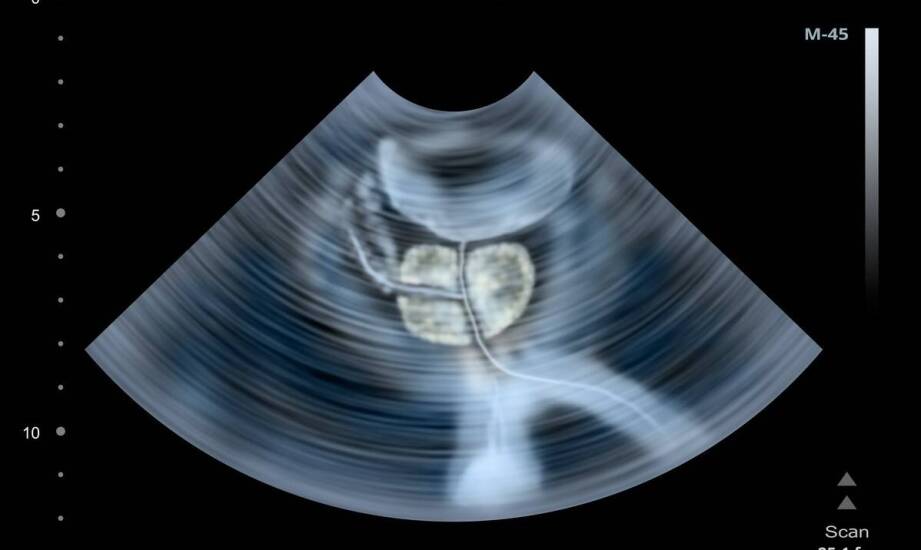

Guz przysadki mózgowej to jeden z najczęściej występujących nowotworów ośrodkowego układu nerwowego, który może prowadzić do poważnych problemów zdrowotnych. Wczesna diagnoza ma istotne znaczenie dla planowania leczenia, a regularne badania kontrolne pozwalają monitorować stan zdrowia pacjentów. Edukacja na temat choroby oraz jej objawów umożliwia aktywne uczestnictwo w procesie terapeutycznym, co jest ważne z punktu widzenia przebiegu leczenia. Warto również pamiętać, że odpowiednie wsparcie ze strony specjalistów może znacząco wpłynąć na jakość życia osób dotkniętych tym schorzeniem.

Guz przysadki mózgowej może powodować różnorodne objawy, które zależą od jego wielkości i lokalizacji. Wczesne symptomy mogą by ć subtelne, ale z czasem stają się bardziej wyraźne. Najczęściej występujące to bóle głowy, zaburzenia widzenia oraz problemy hormonalne. Bóle głowy są często uporczywe i nie ustępują po zażyciu leków przeciwbólowych. Zaburzenia widzenia mogą obejmować podwójne widzenie lub utratę pola widzenia. Problemy hormonalne wynikają z nadmiernej produkcji hormonów przez guz lub ucisku na zdrową tkankę przysadki. Kiedy operacja guza przysadki mózgowej staje się konieczna? Pacjent powinien zgłosić się do lekarza w momencie zauważenia objawów utrzymujących się przez dłuższy czas. W przypadku dużych zmian lub tych powodujących poważne dolegliwości interwencja chirurgiczna może być rozważana. Systematyczne badania profilaktyczne umożliwiają śledzenie kondycji zdrowotnej oraz wczesne wykrywanie ewentualnych nieprawidłowości.